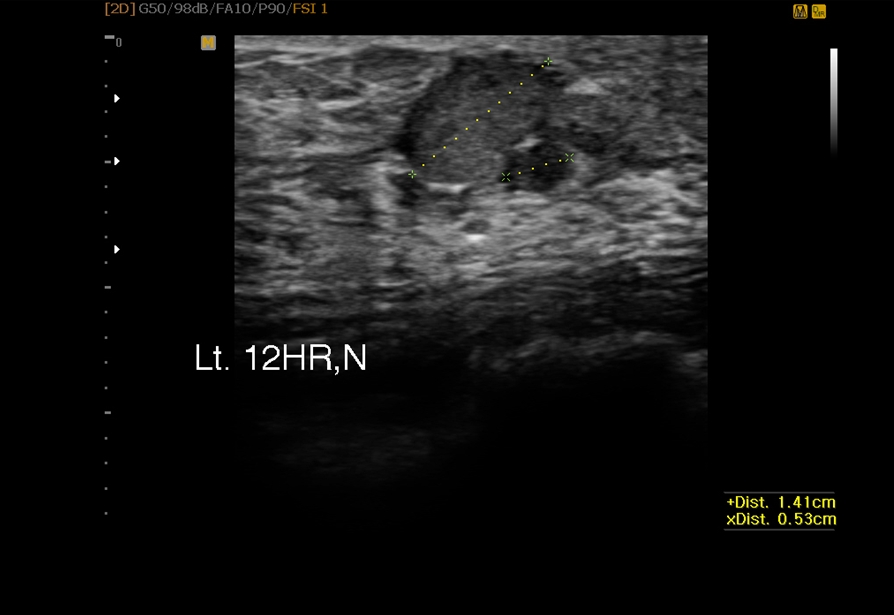

Á¶Á÷°Ë»ç(¸¾¸ðÅè)Ŭ¸®´Ð